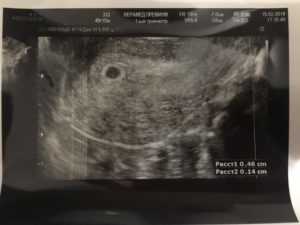

Расшифровка первого обследования

Во время первого ультразвука специалист-диагност выявляет образование с повышенной эхогенностью. Так выглядит плодное яйцо, величина которого позволяет судить о сроке данной беременности.

Ещё на мониторе будут видны желточный мешок, расположение зародыша, толщина внутреннего слоя матки. Врачи убедятся в отсутствии у женщины воспалений, полипов, кист и опухолей. Расшифровывать данные должен только профильный диагност.

Во время первого УЗИ обнаруживаются:

- круглое или каплевидное образование с низкой эхогенностью размером 3-5 мм. Его размер определяет срок;

- тонкая оболочка вокруг развивающегося ребёнка;

- жёлтое тело – оно вырабатывает прогестерон, способствующий сохранению плода.